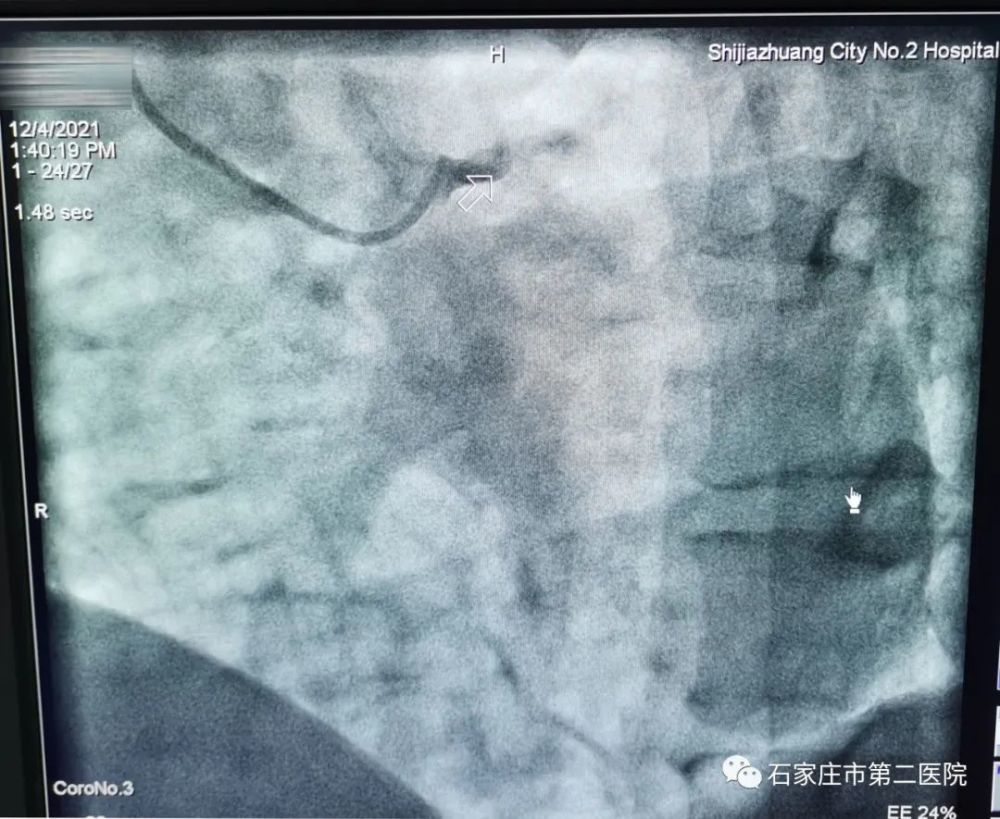

造影显示之前的判断十分准确,患者的左冠状动脉根部已完全闭塞。

这位36岁的小李(化名),身高178厘米,体重达210斤。介入手术中,因为小李的血栓负荷重,前降支近端95%狭窄,用球囊扩开堵塞的血管后,血管竟然再次闭塞。

左图:手术前,左主干远端血管未显影